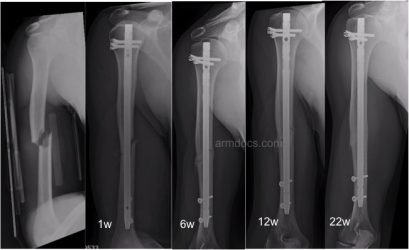

An appointment will be arranged for you to be seen 2 weeks after the procedure.  Follow-up is required for at least 6-12 months after surgery or until a satisfactory recovery is achieved. X-rays will be performed at intervals to monitor fracture healing.

Appearance and progress after nailing